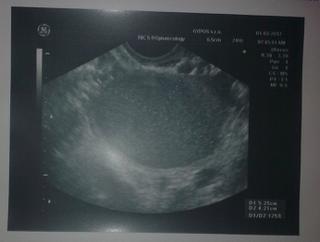

@fifitko25 @kikaneu @chorucka @purina12345 babenky, takto to ináč u mňa dolu vyzerá - vrchný je pravobok a ten je ukážkový a spodný je pokazený ľavobok v zlom stave 😠 a ten samostatný je ľavobok spred dvoch týždňov s mierami viac ako 5cm...